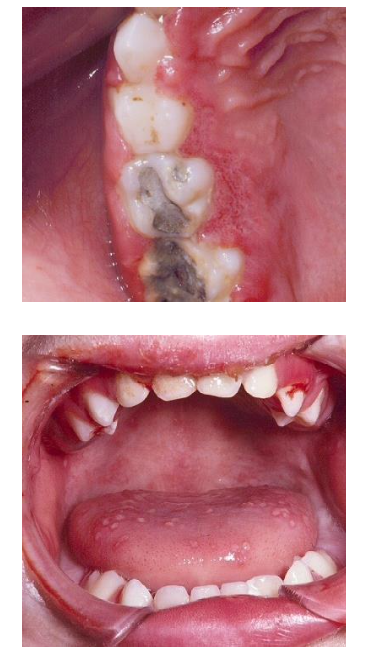

Odontogenic Infections: Acute infections present with fever, facial swelling, distress, and possible dehydration. Chronic infections may be asymptomatic but can cause a mobile or discolored tooth, halitosis, or a sinus tract.

F.A.C.E.S.

F – Fever (Acute Infection)

The body’s response to infection, leading to increased temperature, often associated with acute odontogenic infections.

A – Asymptomatic (Chronic Infection)

Chronic infections may not show any obvious symptoms but can still cause problems like tooth mobility or discoloration.

C – Chronic Infections (Sinus Tract/Discolored Tooth)

Chronic odontogenic infections can present with a mobile or discolored tooth and a sinus tract that may drain.

E – Edema (Swelling) (Acute Infection)

Swelling in the face or oral tissues is a hallmark of acute odontogenic infections.

S – Sinus Tract (Chronic Infection)

A chronic infection may form a sinus tract, leading to drainage of pus or fluid from the infected area.